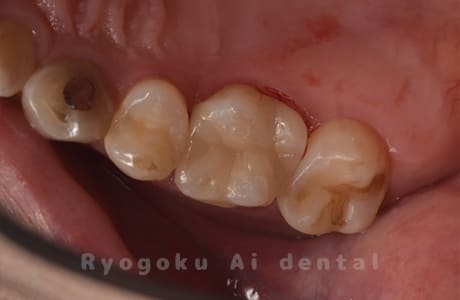

Case08

-

- 原因

- 虫歯

- 治療内容

- セラミックインレー

- 治療費用

- 77,000円

奥歯の黒い点が気になるということで来院された患者さんです。白い詰め物を外したところ、虫歯が中で大きく広がっていたため、患者さんと相談し、セラミックインレーで治療を行いました。

<リスク・副作用>

過度の咬合や衝撃で割れることがあります。